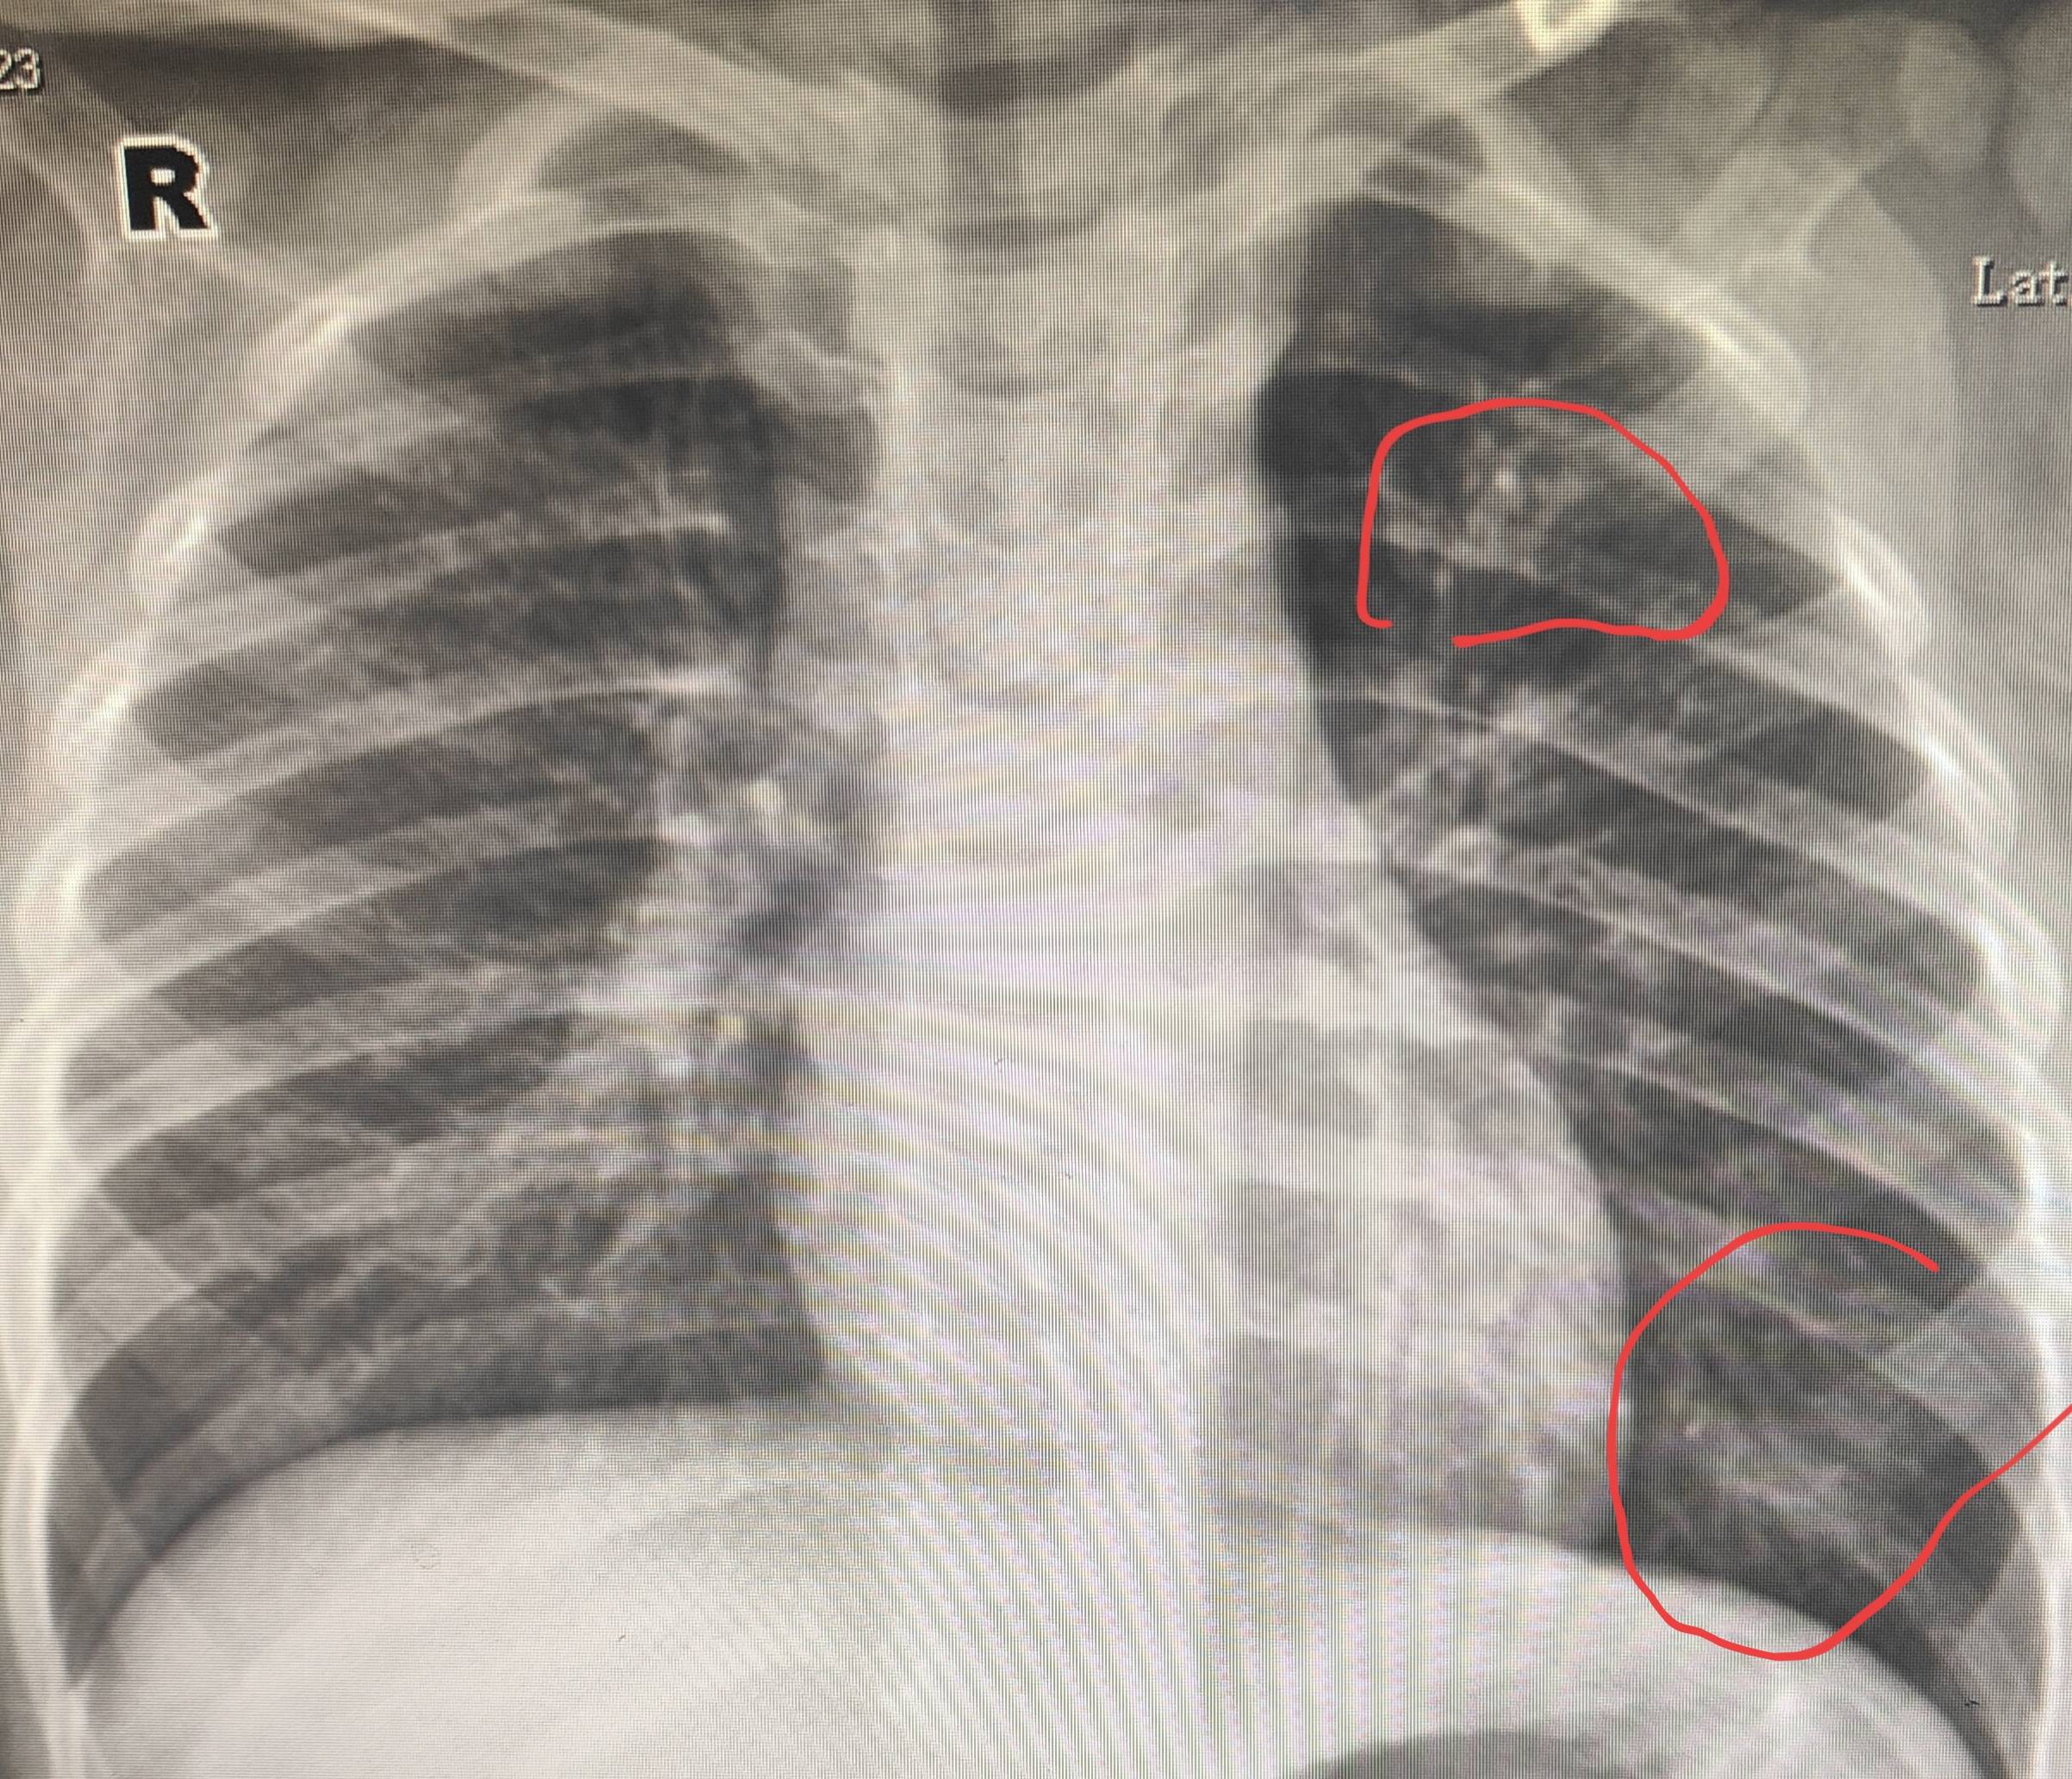

肺炎x光片表现

这种影像学表现虽不一定是重疾信号,但若出现在肺上叶,可能与特殊病变

这么明显的肺炎,我当时怎么就没想到?那些经验去哪儿了?